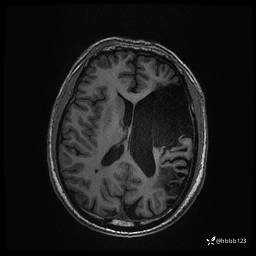

患者男,43岁。

简要病史:癫痫患者复诊,昨日发作5-6次,建议住院进一步治疗。

入院完善脑癫痫组合序列:

T2: